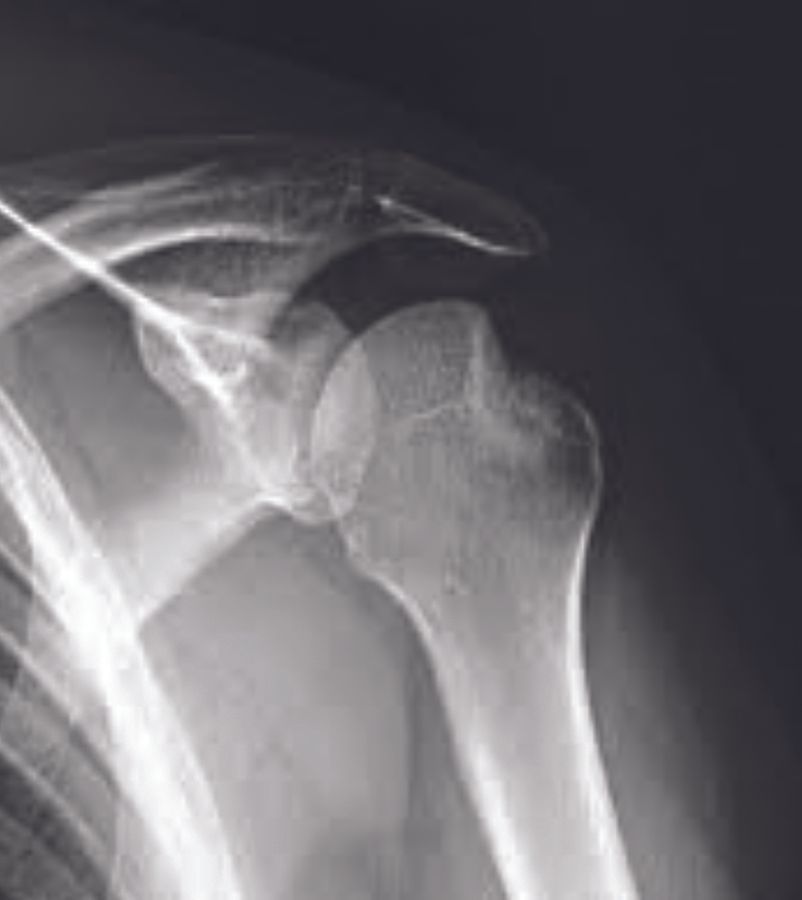

Mise au point Y a-t-il encore des indications à combler les encoches de Malgaigne sous arthroscopie ? , Claire Bastard Hôpitaux Universitaires Henri Mondor, AP-HP, Créteil, France , Geoffroy Nourissat Hôpital Saint-Antoine, 75012 Paris, France 🖂 gnourissat@wanadoo.fr N°289 - Décembre 2019 ● 11 min de lecture

Technique Le bankart augmenté , Aurore Blancheton Clinique Maussins-Nollet, 67 Rue de Romainville 75019, Paris, France , Geoffroy Nourissat Hôpital Saint-Antoine, 75012 Paris, France 🖂 gnourissat@wanadoo.fr N°289 - Décembre 2019 ● 7 min de lecture